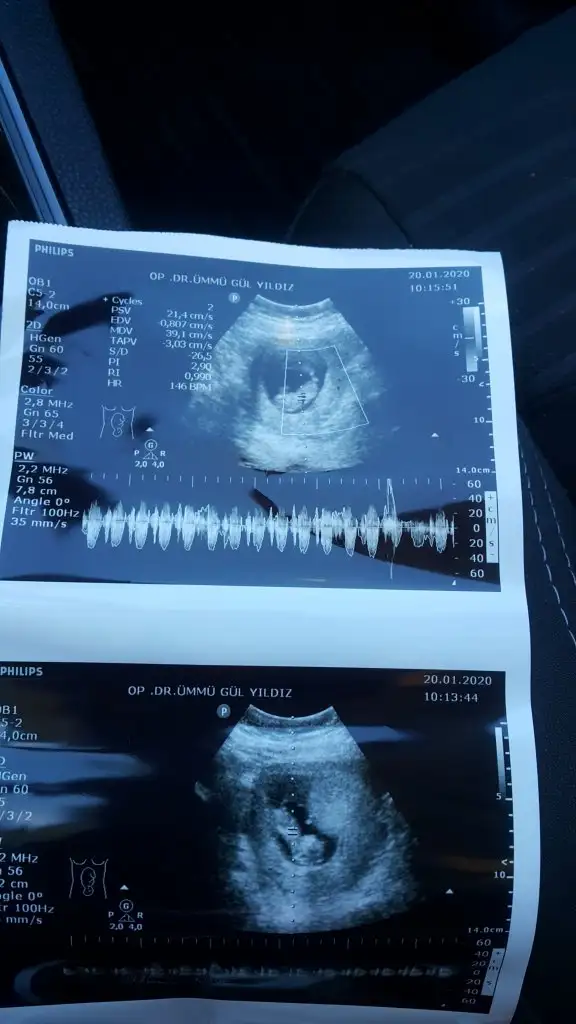

Screenshot_20200120-154357.webp

mrhaba lütfen yorumlarmisiniz sizce kızmı erkekmi bi arkadas icin soruyorum